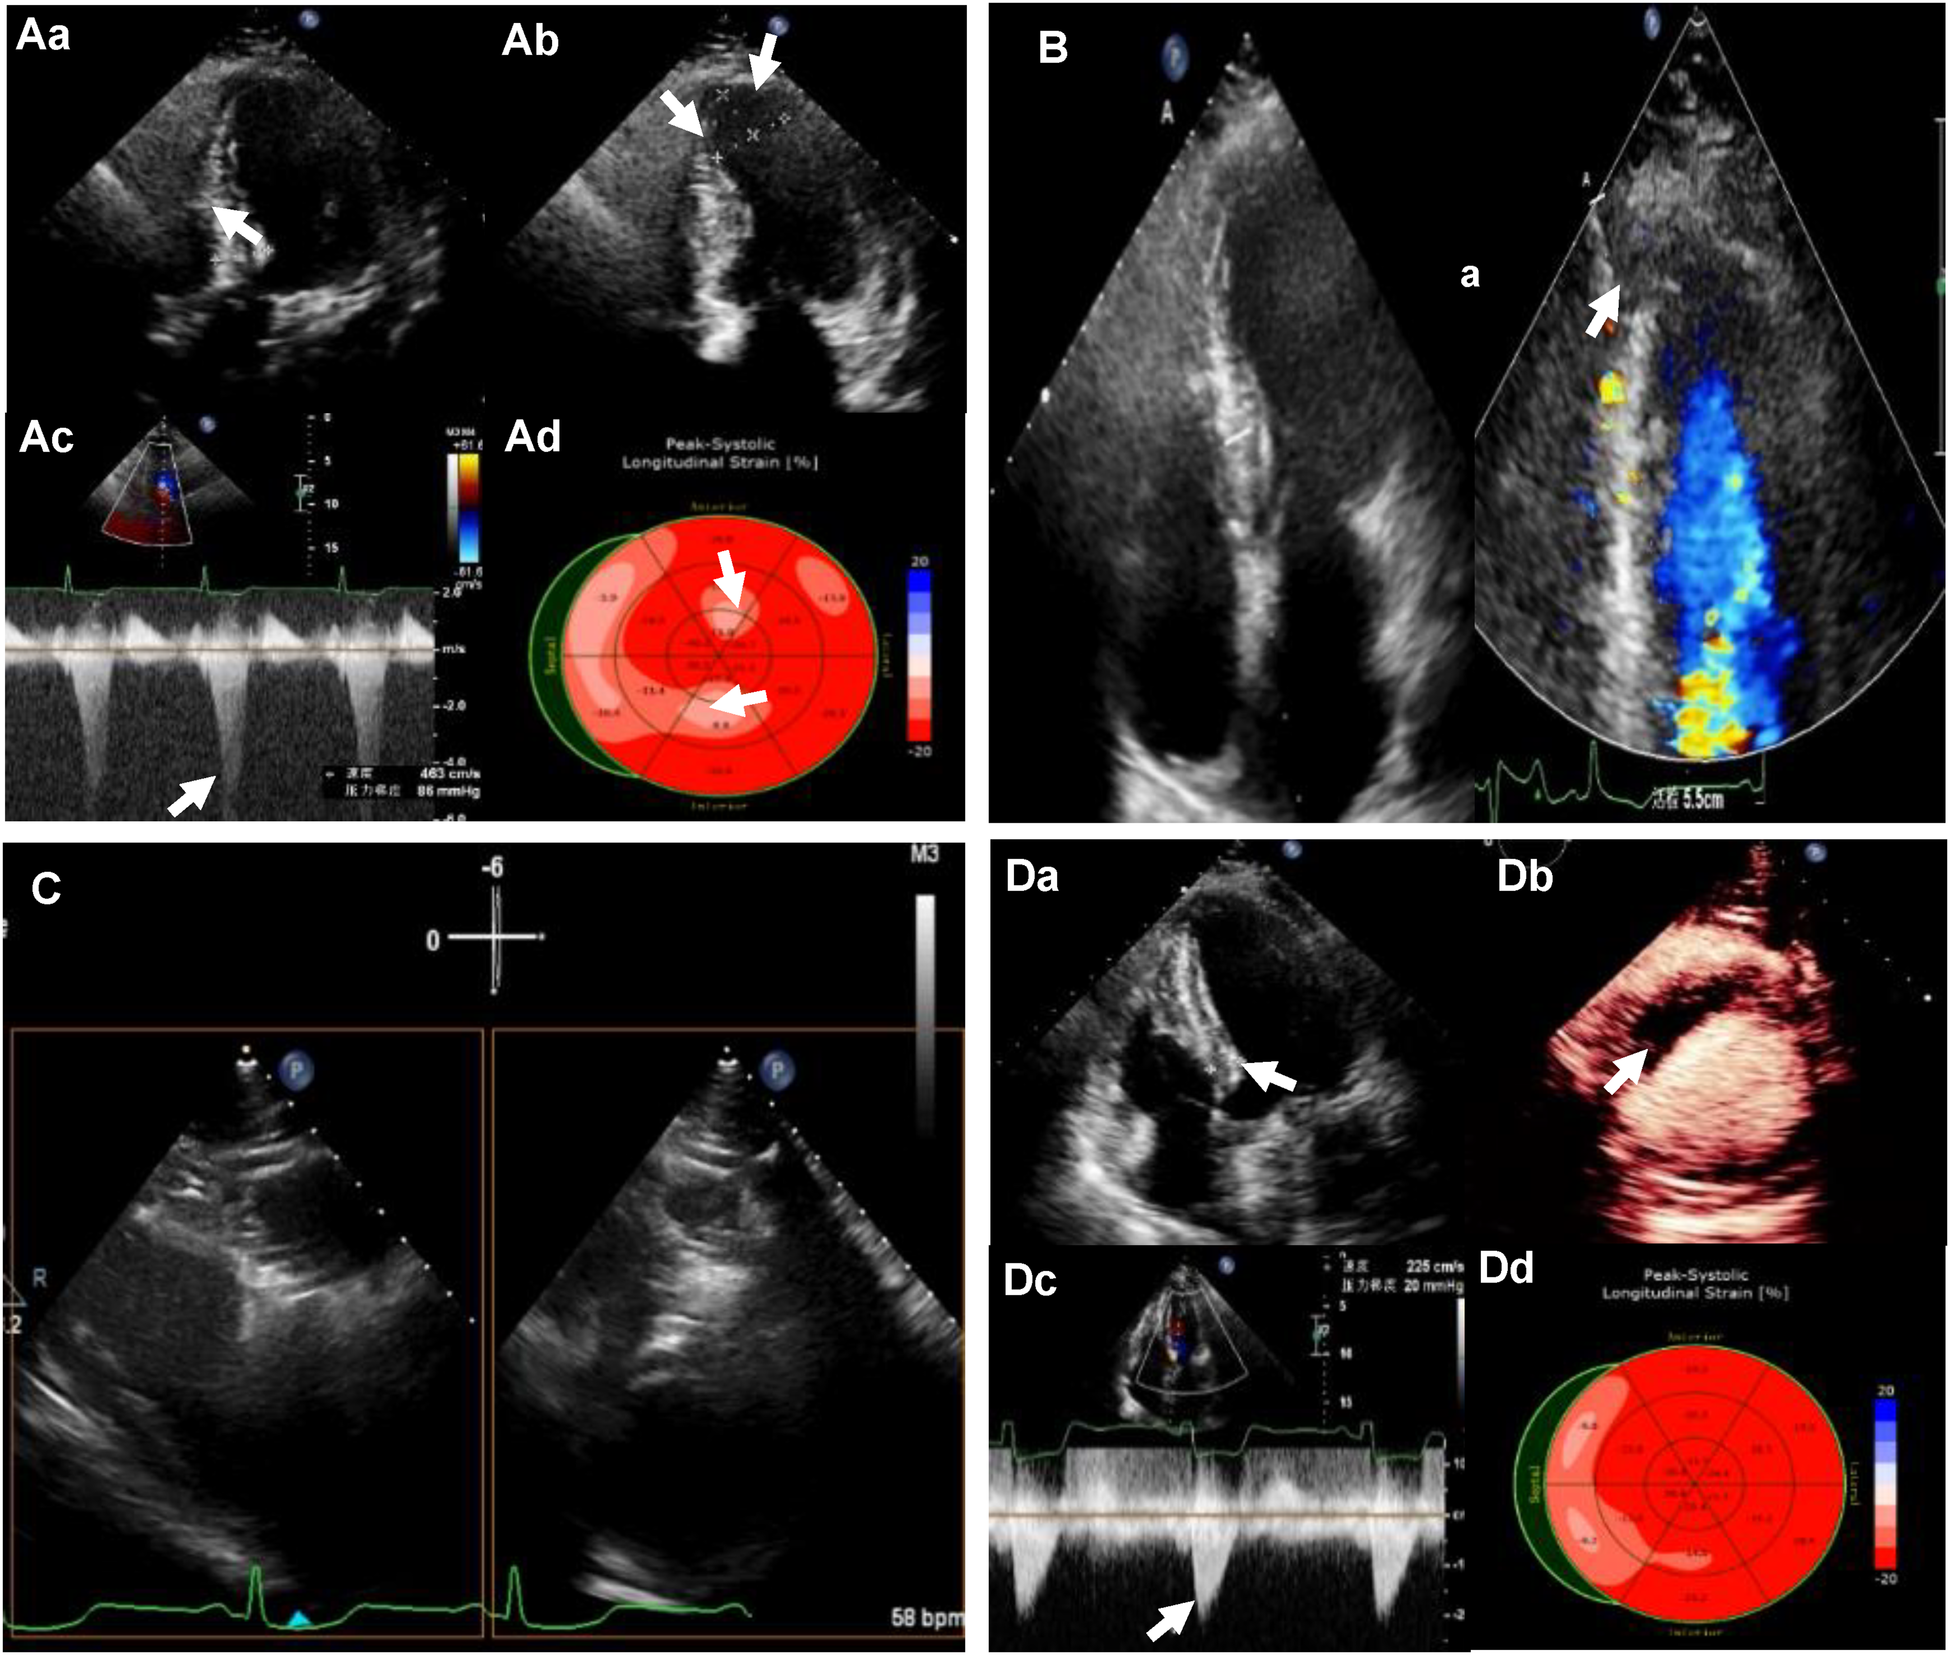

Figure 1

(Aa) Preoperative transthoracic echocardiography (TTE): left ventricular (LV) septal thickness of 20mm; (Ab) the extent of ventricular aneurysm; (Ac) left ventricular outflow tract (LVOT) obstruction at rest; (Ad) reduced strain value of local LV apex by strain echocardiography (SE). (B) LV apical entrance of the ablation needle guided by TTE. (C) Bi-plane showing ablation needle position. (Da) LV septal thickness of 12 mm after ablation; (Db) myocardial contrast-enhanced echocardiography (MCE) showing a contrast filling defect in the ablation zone; (Dc) LVOT gradient of 20 mm Hg after the ablation; (Dd) LV apical systolic synchrony detected by SE.

A 57-year-old woman presented with worsen dyspnea after exercise for 5 years. TTE revealed thickening of the interventricular septum (up to 20 mm) and increased flow velocity in the left ventricular outflow tract (LVOT) with a peak velocity of 4.52 m/s and evaluated peak pressure gradient of 85 mmHg. Localized thinning of the ventricular wall at the apex, approximately 5 mm in thickness, was noted, with mild paradoxical motion, covering an area of approximately 19 mm × 30 mm. M-mode echocardiography revealed positive systolic anterior motion of the mitral valve (SAM) and moderate mitral regurgitation. 2-D STE examination were applied for the strain evaluation pre- and post-operation. Pre-operative STE demonstrated the lowest strain value in the basal interventricular septum, decreasing to −5.9%, and the lowest strain value in the left ventricular apex, decreasing to −11.9% (Figure 1A). The patient reported experiencing chest discomfort, shortness of breath, occasional precordial pain, along with fatigue and palpitations, particularly after physical activity. These symptoms would alleviate with rest. Coronary angiography indicated normal origins and courses of the left and right coronary arteries without significant stenosis. Cardiac magnetic resonance imaging (MRI) findings suggested a diagnosis of hypertrophic cardiomyopathy with asymmetrical myocardial hypertrophy, interstitial fibrosis, and left ventricular outflow tract (LVOT) obstruction (Figure 2A). Initial laboratory investigations revealed elevated NT-proBNP levels at 854 pg/ml and cTNT levels at 12.19 ng/L. The electrocardiogram showed sinus rhythm with abnormal Q waves in leads I, II, avL, and V3–V6, as well as horizontal ST-segment depression of 0.05–0.2 mv in leads I, II, III, avF, and V3–V6, accompanied by bidirectional T-wave changes in the same leads. The patient was classified as NYHA III in terms of functional capacity (Figure 2E). Despite undergoing optimal medical therapy, the patient continues to experience symptoms of heart failure, including chest pain, chest tightness, and shortness of breath, classified as NYHA Class III. According to a multidisciplinary consultation, it was recommended that the patient undergo surgical resection and alcohol septal ablation. However, the patient was unwilling to undergo cardiac surgery. Although coronary alcohol septal ablation presents itself as a viable alternative, the ventricular septal branch and location of myocardial hypertrophy is incongruent in this patient. This inconsistency renders it less effective and potentially raises the risk of pacemaker reliance, making it unsuitable for targeted alcohol injection. As a result, we proposed a novel treatment approach in our center, employing radiofrequency ablation for HOCM-LVAA, Liwen procedure.

The patient undergone Liwen procedure under general anesthesia in the supine position. Considering the ventricular aneurysm, we attempted the modified needle technique guided by TTE, in which the approach was reverse insertion to avoid pericardial tamponade caused by insertion into the left ventricle (Figure 1B). The location and characteristics of the aneurysm necessitated a specific approach when choosing the Liwen procedure. Due to the aneurysm's location and features, we opted for a modified insertion approach, transitioning from the conventional B-line approach to the A-line approach. We also rotated the ultrasound probe by 180° and carefully positioned the needle tip along the aneurysmal wall to target the basal interventricular septum for ablation. The presence of the ventricular aneurysm compelled us to pay special attention to the insertion direction and needle tip placement within the aneurysmal myocardium during the Liwen procedure to avoid inadvertent entry into the cardiac chamber and the risk of pericardial tamponade (Figure 1C). The ACT-1530 radiofrequency needle was advanced along the ventricular wall to the hypertrophic portion of the anterior septum under ultrasound guidance. We employed the Philips X5-1 probe with X-plane dual-plane functionality to guide the needle tip's positioning, ensuring it was located in the basal portions of the anterior septum (Zone I, Zone II, Zone III). Radiofrequency energy was then applied, with a maximum power of 80 W, 80 W, and 105 W for each respective zone, and treatment durations of 7 min, 8 min, and 3 min. After ablation, myocardial contrast echocardiography revealed a contrast filling defect in the ablation zone of the interventricular septum. One week later, the thickness of the myocardium in the interventricular septum decreased from 20 mm to 12 mm, and LVOT obstruction was significantly relieved (peak gradient of 20 mmHg). STE showed LV systolic synchrony was achieved, and the apical aneurysm returned to normal appearance of morphology (Figure 1D). One year post the procedure, STE showed an increase in strain values in the basal interventricular septum, reaching −17.5%, and a significant recovery in strain value in the left ventricular apex, returning −22.3%” (with the anterior wall as a reference) (Figure 2B). Through the stress echocardiographic examination, we detected an increased LVOT with a peak velocity of 5.5 m/s and a peak pressure gradient of 121 mmHg in this case. However, 1 year after the procedure, stress echocardiography showed a reduced flow velocity in the LVOT, with a peak velocity of 2.5 m/s and a peak pressure gradient of 25 mmHg (Figure 2F). One-week postoperative assessment, laboratory results indicated NT-proBNP levels at 907 pg/ml and cTNT levels at 5,335 ng/L. Subsequent follow-up examinations at 1 year and 2 years post-procedure showed a reassuring trend with NT-proBNP levels at 801 pg/ml and 657 pg/ml, respectively, and cTNT levels at 13.7 ng/L and 14.8 ng/L, respectively. Postoperative electrocardiography revealed sinus rhythm with horizontal ST-segment depression of 0.05–0.20 mv in leads I, II, III, avF, and V4–V6, with a P-wave duration of 122 ms. Follow-up electrocardiograms at 1 year and 2 years post-procedure continued to show sinus rhythm with horizontal ST-segment depression of 0.05–0.15 mv in leads I, II, avF, and V3–V6, with a P-wave duration of 122 ms (Figure 2C).